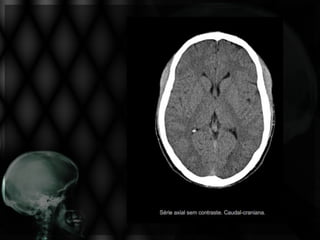

AVE HEMORRÁGICO

LEMBRE!

A     metabolização     do      hematoma

parenquimatoso acaba por diminuir a sua

densidade, resultando em região hipodensa

residual!

À RM o sinal depende

da fase pós-AVE.

HIDROCEFALIAS

Com Derivação

Ventriculoperitoneal

EDEMA CEREBRAL